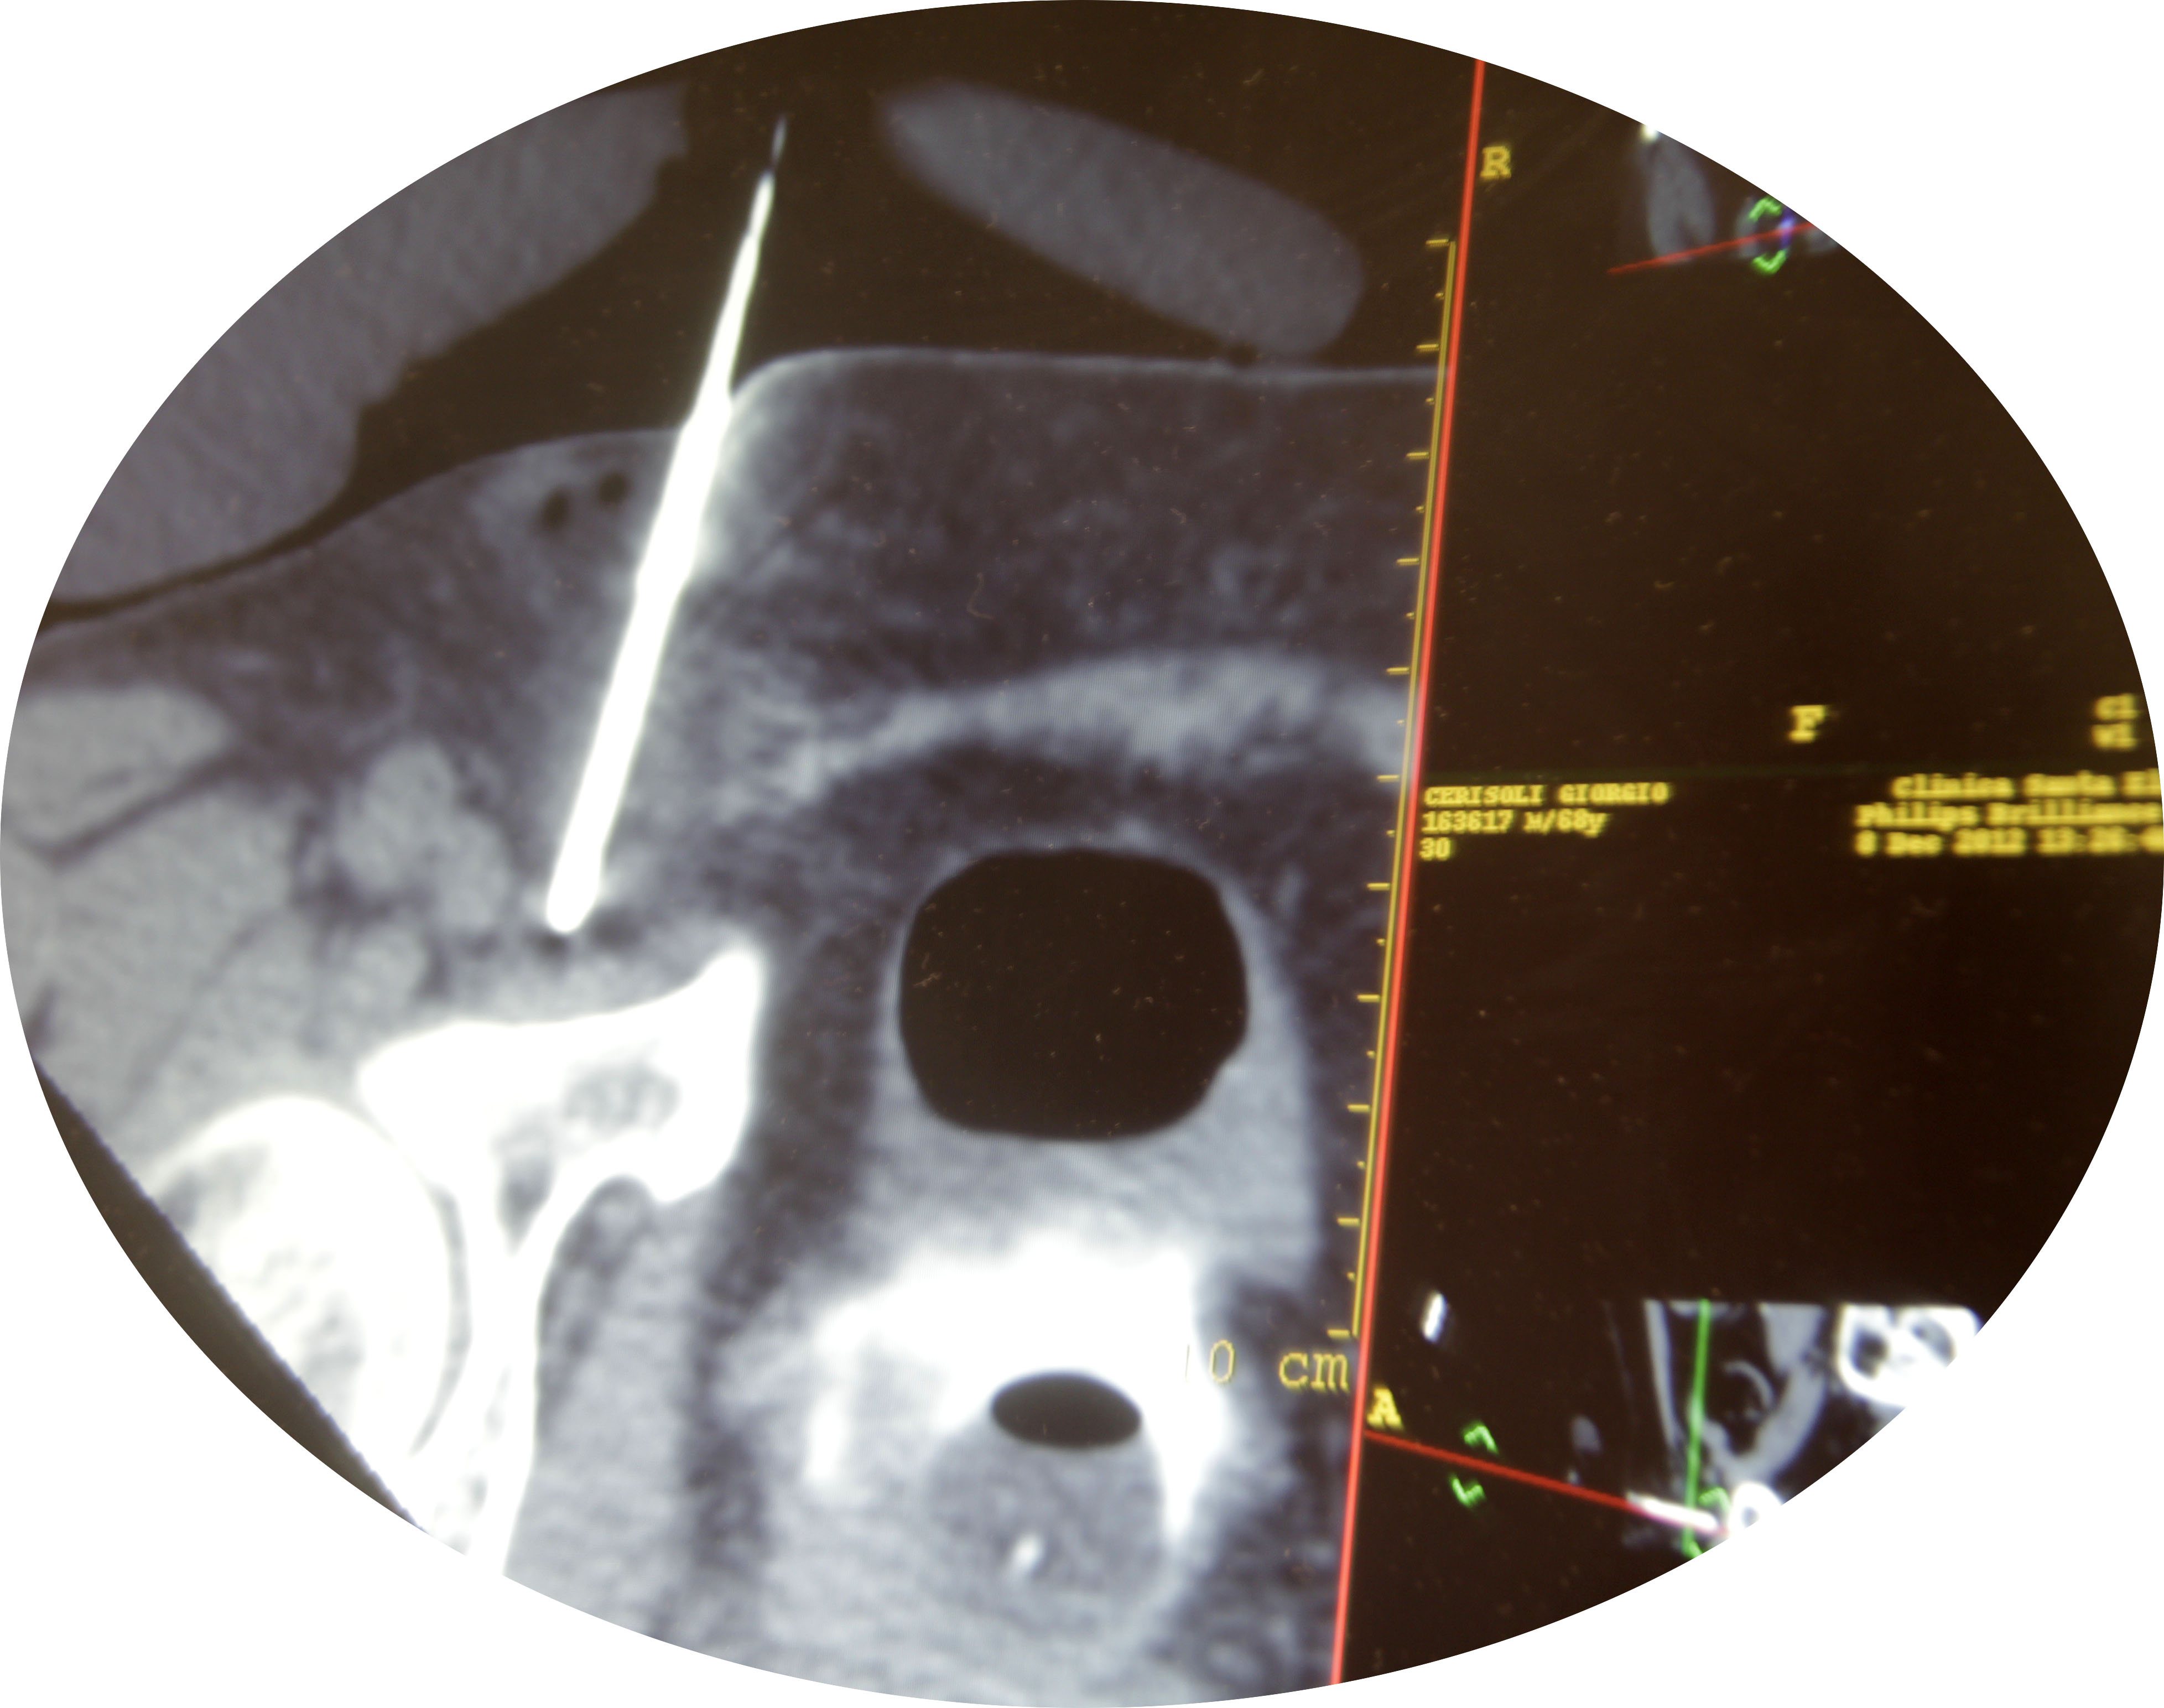

-Cáncer de Riñón mediante TAC y ecografía conducida